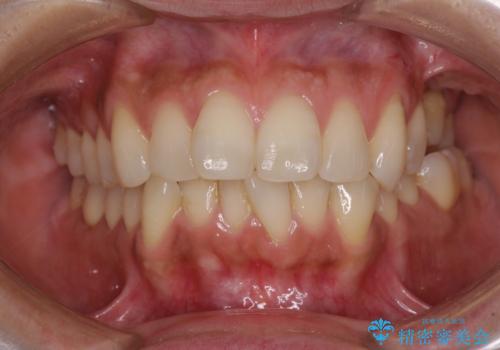

インビザラインによる矯正治療と奥歯のインプラント治療

- 全体的なデコボコと、以前抜歯した歯のスペースを閉じた部分が気になるとのことで来院された患者様です。

左上第一大臼歯を抜歯した際に、スペースを閉じたそうですが、歯が傾斜してものが挟まって不快とのことでした。

インビザライン矯正で全体の歯列と整えるとともに、左上第一大臼歯部にはスペースを作り、インプラントによる補綴治療を行うこととしました。

歯の傾斜が改善され、インプラントによるクラウンが装着されたことで、物が挟まることもなくなりました。